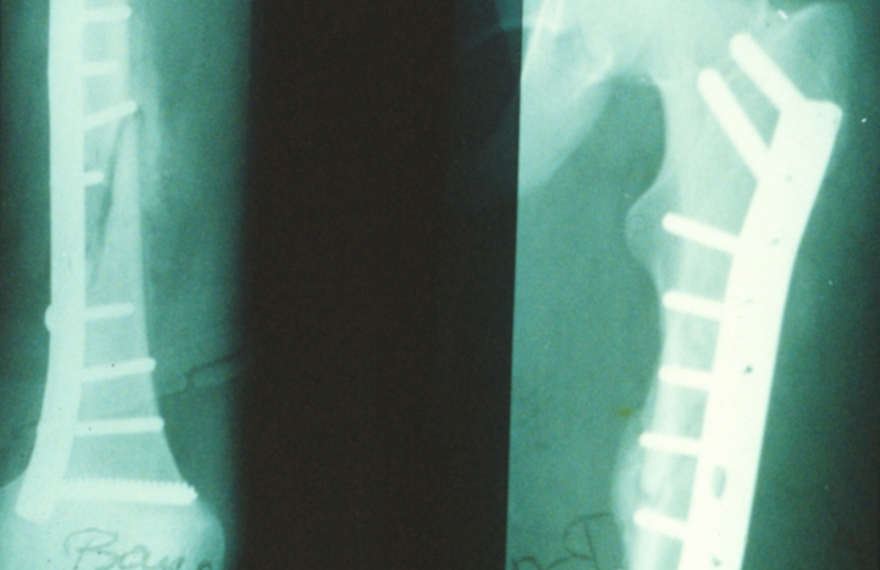

Durchschuss beider Oberschenkelknochen

Röntgenbild nach beidseitiger Osteosynthese. Patient bewegt beide Beine wieder ohne Einschränkungen.